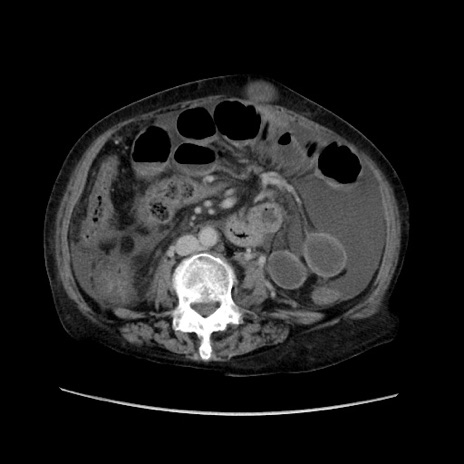

冠状断像